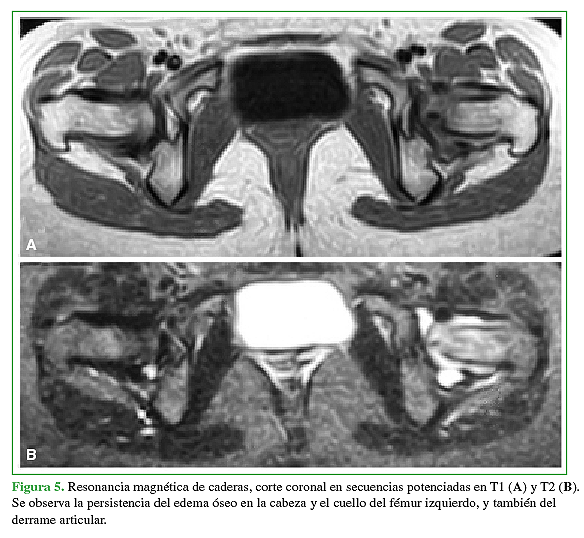

Se presenta un caso de un paciente femenino de 22 años con dolor en cadera izquierda de larga evolución sin antecedentes reelevantes.Descargas